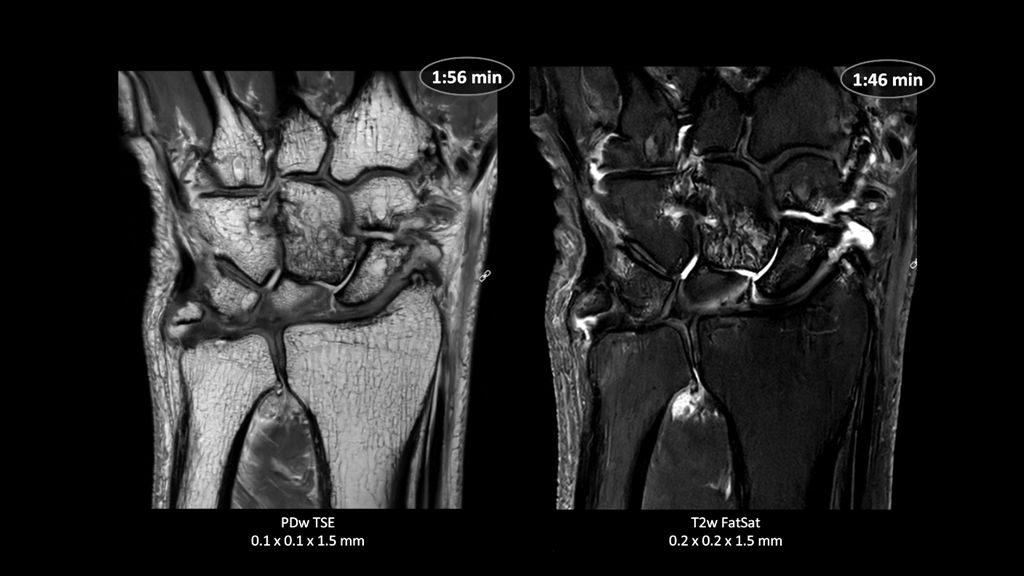

2. Reconstruction technology Compared to conventional (SENSE/ Compressed SENSE, SmartSpeed AI) imaging. Sharpness was evaluated with phantom scanning.

3. dStream based systems, not available for Prodiva and Multiva systems.